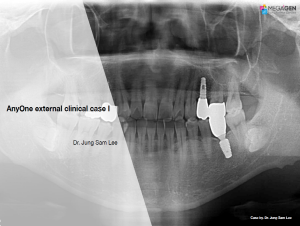

Dr. Achraf Souayah,Edentulous,Aesthetic zone,Maxillary Anterior,Maxillary Posterior,Mandibular Anterior,Mandibular Posterior,Guided surgery,Sinus Elevation,Immediate Placement,AnyRidge,Overdenture system,Meg-Rhein,MILA Kit,Clinical case